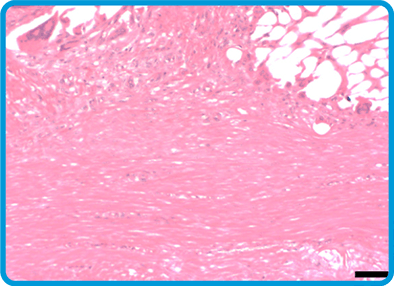

The BioBrace® Implant Filled With New Tissue

Oriented New Tissue Generation: The advanced 3D structure of BioBrace® provides internal channels that naturally guide alignment of new fibers.